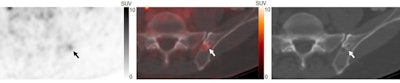

A 60-year-old patient with biochemically recurrent prostate cancer and a PSA level of 3.9 ng/mL. Axial F-18 DCFPyL PET (left), F-18 DCFPyL PET/CT (middle), and CT (right) images show a single subtle PSMA-avid uptake with SUVmax of 3.9 in the left iliac bone and mixed sclerotic/lytic CT features (arrows). This indeterminate bone lesion (IBL) was stable for four months and negative on four other staging modalities; thus, the IBL was determined to be benign. Image courtesy of the Journal of Nuclear Medicine.Two nuclear medicine physicians categorized the IBLs on the images as either benign, malignant, or equivocal, noting lesion locations' maximum standard uptake values (SUVmax) for each.